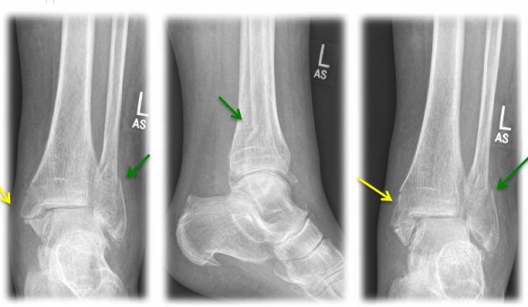

Fig. 3) "Bimalleolar ankle joint fracture" left x-rayed in 3 planes (a.p., lateral, internal rotation) with an internal ankle fracture (yellow arrow) and a spiral external ankle fracture (green arrow)